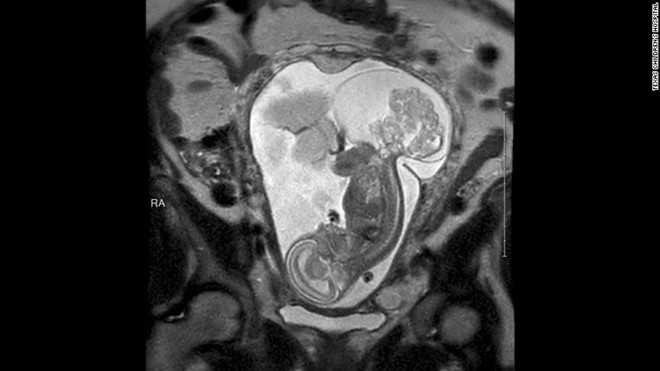

Khối u của bào thai có thể nhìn thấy trong tấm ảnh scan

Thời điểm Tiến sỹ Cass tiến hành phẫu thuật bào thai, chị Boemer đang mang thai ở tuần 23 và 5 ngày. Lúc này, khối u gần như lớn hơn cả bào thai.